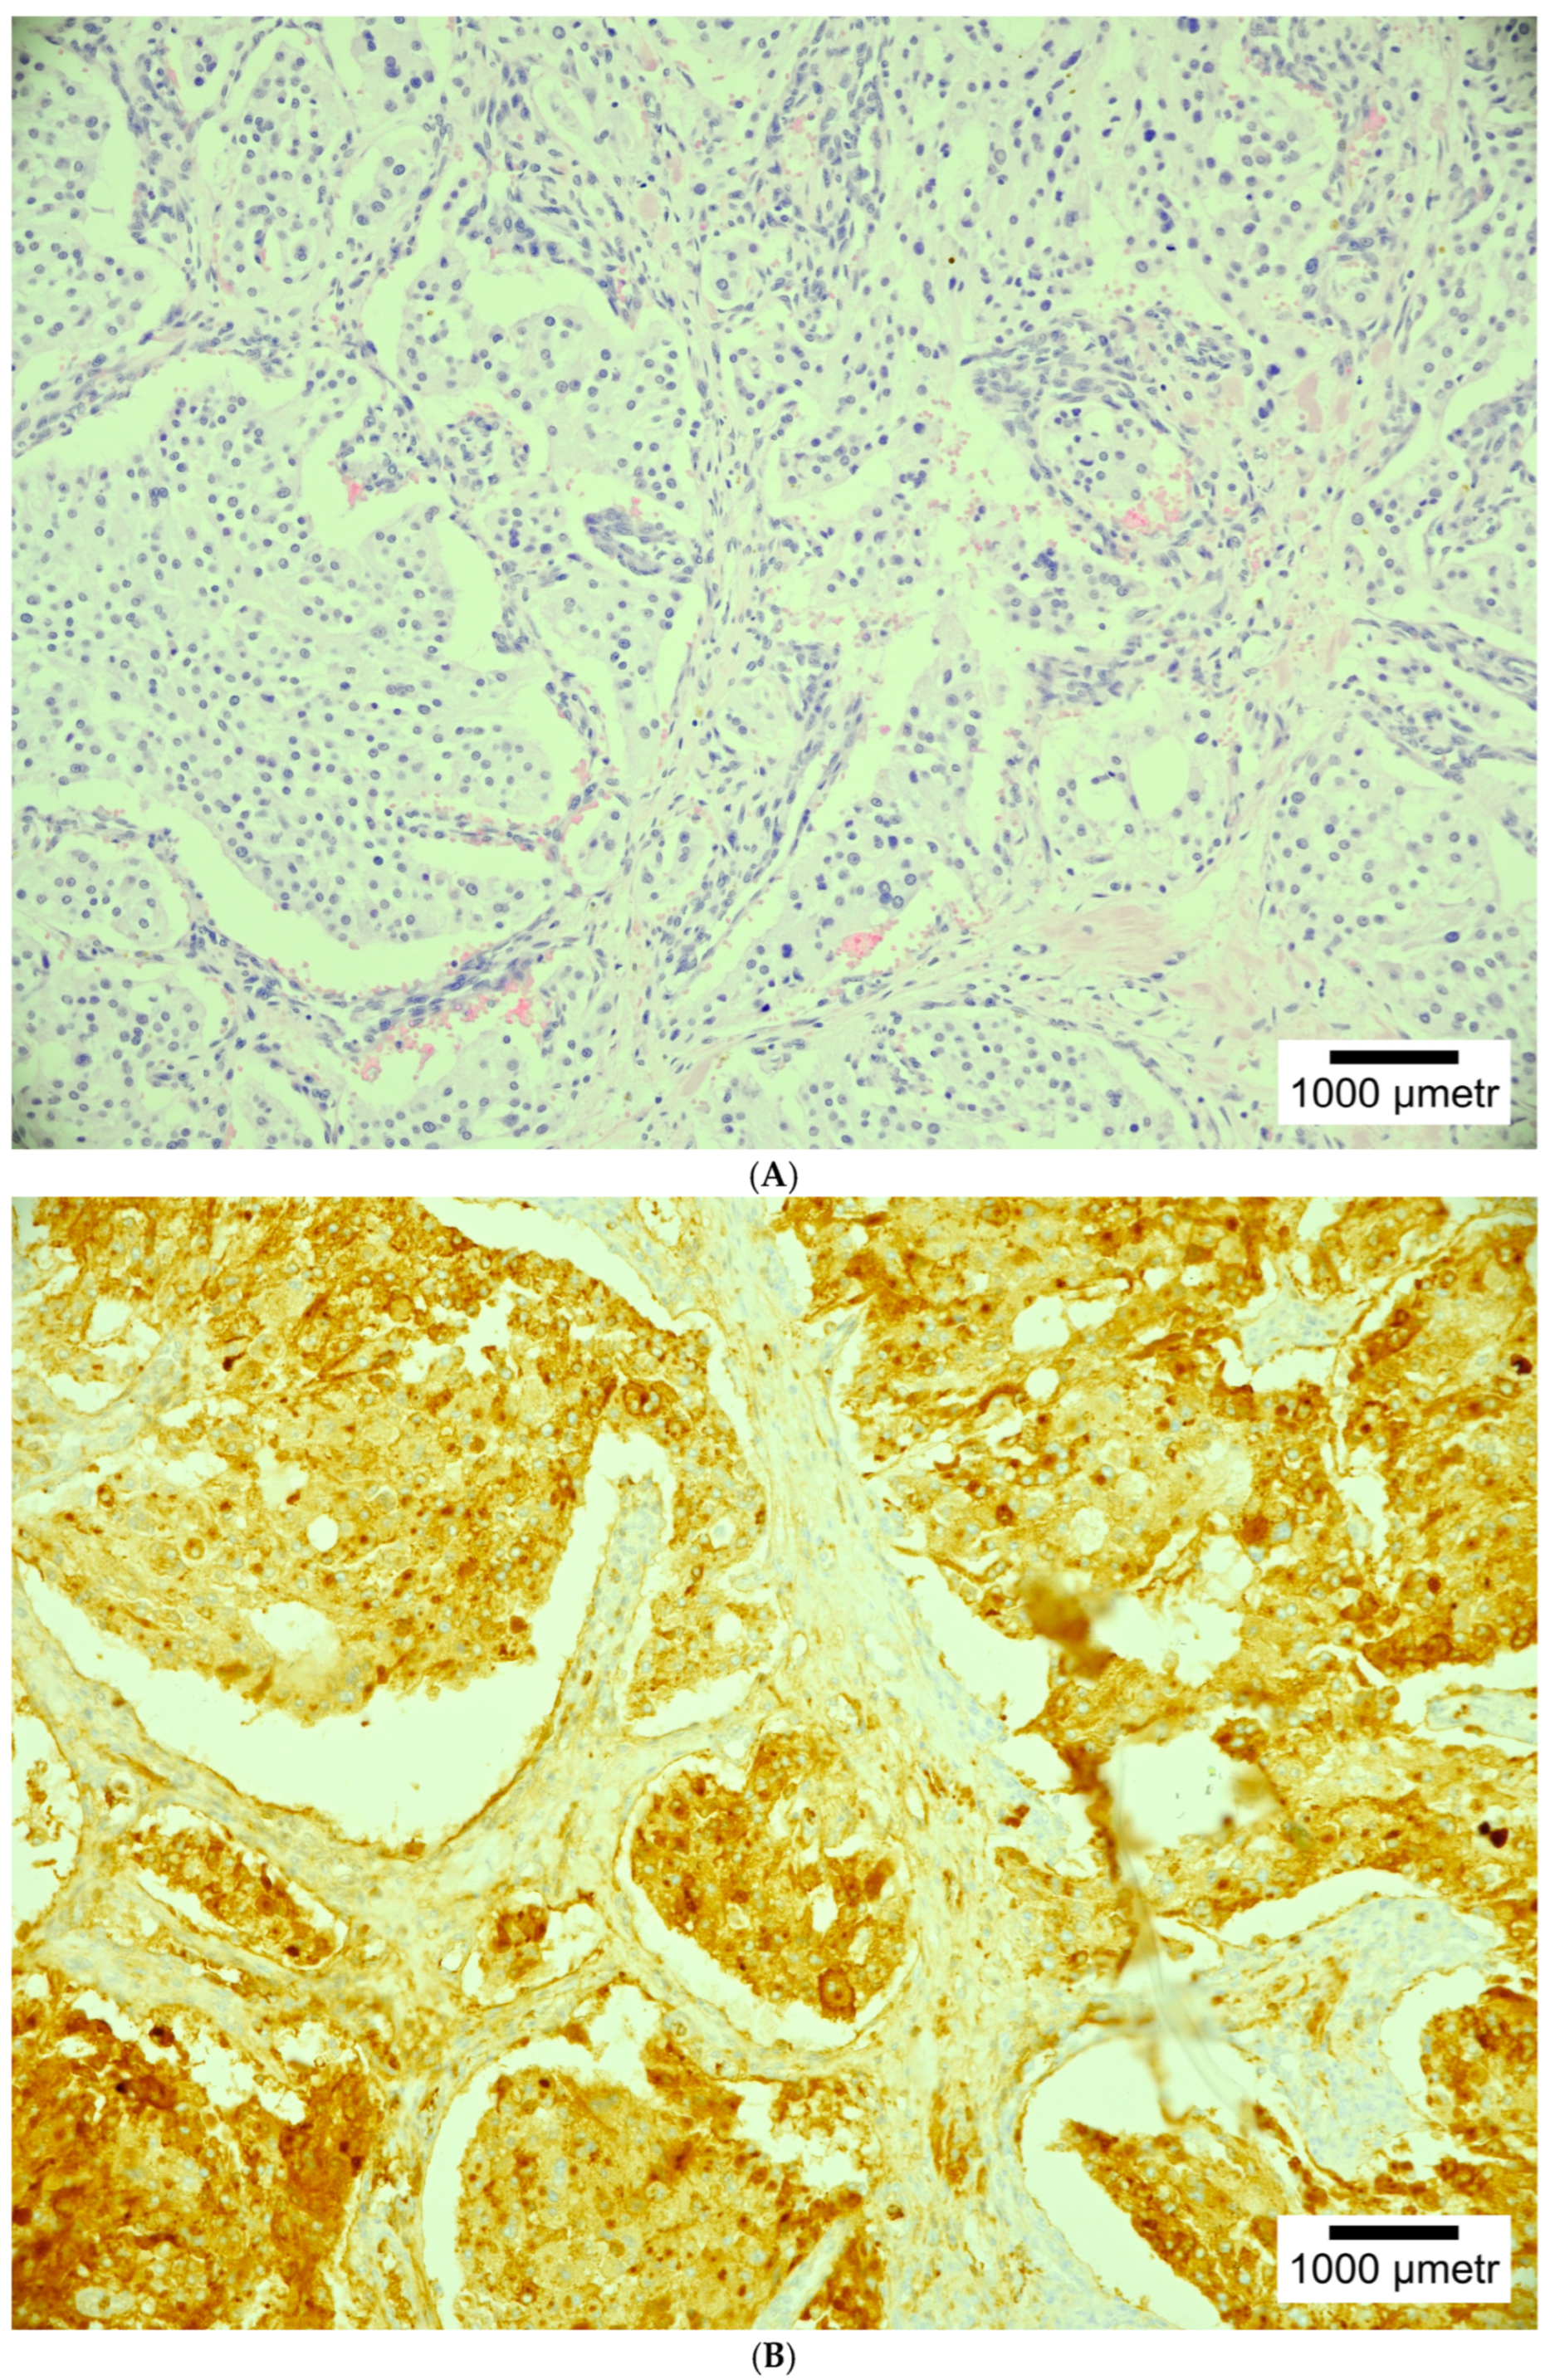

4. Histopathology